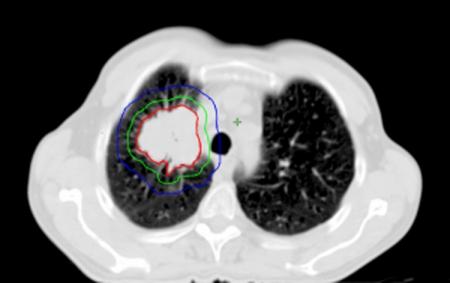

Effective treatment for carcinoma of the lung remains one of the biggest challenges in oncology. Radical radiotherapy may be a curative option for patients who are unsuitable for radical surgery either because of disease stage or because of co-morbidity. Long-term disease control with radical radiotherapy is disappointing with only about 6% of patients treated being alive at 5 years. Technological advances involved in the planning and delivery of radiotherapy may improve this. The advent of conformal radiotherapy, utilizing computed tomography and three-dimensional planning systems, allows much more accurate shaping of the radiation fields. This greater accuracy of target volume definition facilitates a reduction in the radiation dose to normal tissues, allowing for dose escalation to the tumour. Delineation of the target volume can be problematic. Conventional CT has limitations in term of distinguishing between benign and malignant tissues, e.g. the size criteria for involved lymph nodes. The oncologist uses a combination of radiological and clinical information when defining the target volume but their radiological interpretation of imaging is inferior to that of a radiologist. The Royal College of Radiologists (RCR) issued guidance in 2004 on the optimal imaging strategies for common cancers. These guidelines address issues regarding the localisation and staging of cancers and treatment planning, and also reporting and training. They recommend the development of closer links between radiologists and oncologists to optimise the interpretation of imaging and target volume definition. This article aims to briefly explain the planning process involved in irradiating lung cancers, highlight problematic areas and suggest ways in which co-operation with radiologists may improve the delivery of radiotherapy and therefore the treatment outcomes for this group of patients.

肺癌的有效治疗仍然是肿瘤学领域最大的挑战之一。对于因疾病分期或合并症而不适于根治性手术的患者,根治性放疗可能是一种治愈性选择。根治性放疗的长期疾病控制效果令人失望,接受治疗的患者中只有约6%能存活5年。放疗计划和实施过程中的技术进步可能会改善这一情况。适形放疗的出现,利用计算机断层扫描和三维计划系统,能够更精确地塑造辐射野。靶区定义的更高准确性有助于减少对正常组织的辐射剂量,从而可以提高肿瘤的照射剂量。靶区的勾画可能存在问题。传统CT在区分良性和恶性组织方面存在局限性,例如受累淋巴结的大小标准。肿瘤学家在定义靶区时会综合运用放射学和临床信息,但他们对影像的放射学解读不如放射科医生。英国皇家放射科医师学院(RCR)在2004年发布了关于常见癌症最佳影像策略的指南。这些指南涉及癌症的定位、分期和治疗计划等问题,以及报告和培训。它们建议放射科医生和肿瘤学家建立更紧密的联系,以优化影像解读和靶区定义。本文旨在简要解释肺癌放疗的计划过程,突出存在问题的领域,并提出与放射科医生合作可能改善放疗实施从而提高这类患者治疗效果的方法。